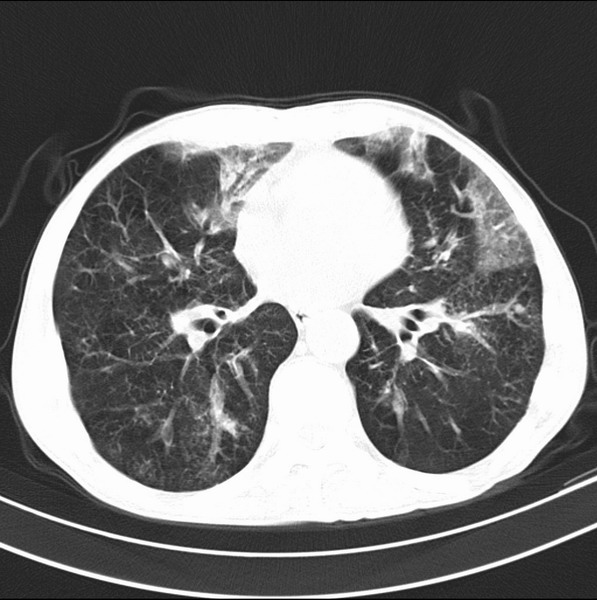

标题: CT19600:能否诊断为转移?

女、55

3年前盲肠癌、一年半前诊断膀胱癌,现在呼吸困难,临床考虑为肺转移

请问胸部ct如何诊断?能否排除淋巴管炎,纵隔窗没有问题。

炎性并间质纤维化

炎性并间质纤维化,请询问病史,如用过平阳霉素或其他化疗药.可能为药物引起的间质纤维化.